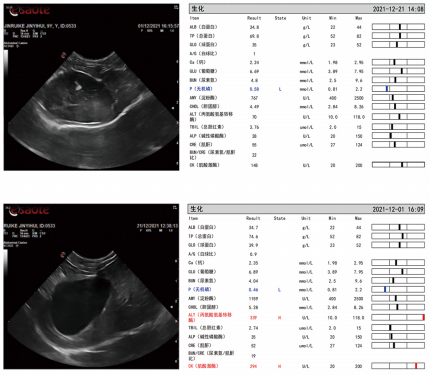

Case 3:

Day 0—Diagnosis

Nausea,vomiting, picky eating, and reduced appetite observed.

Biochemical tests showed elevated ALT levels; ultrasound revealed bile sludge in the gallbladder, and pancreatitis markers were mildly elevated.

Week 3—Visible Improvement

Ultrasound showed a significant reduction of gallbladder sludge.

Vomiting subsided, appetite improved, stool color normalized, and overall condition recovered.

ALT(U/L):339→70